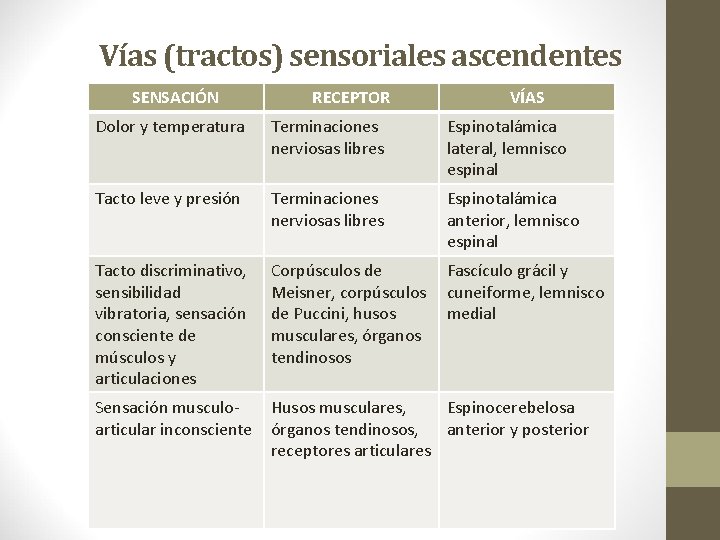

Vías (tractos) sensoriales ascendentes SENSACIÓN RECEPTOR VÍAS Dolor y temperatura Terminaciones nerviosas libres Espinotalámica lateral, lemnisco espinal Tacto leve y presión Terminaciones nerviosas libres Espinotalámica anterior, lemnisco espinal Tacto discriminativo, sensibilidad vibratoria, sensación consciente de músculos y articulaciones Corpúsculos de Meisner, corpúsculos de Puccini, husos musculares, órganos tendinosos Fascículo grácil y cuneiforme, lemnisco medial Sensación musculoarticular inconsciente Husos musculares, Espinocerebelosa órganos tendinosos, anterior y posterior receptores articulares